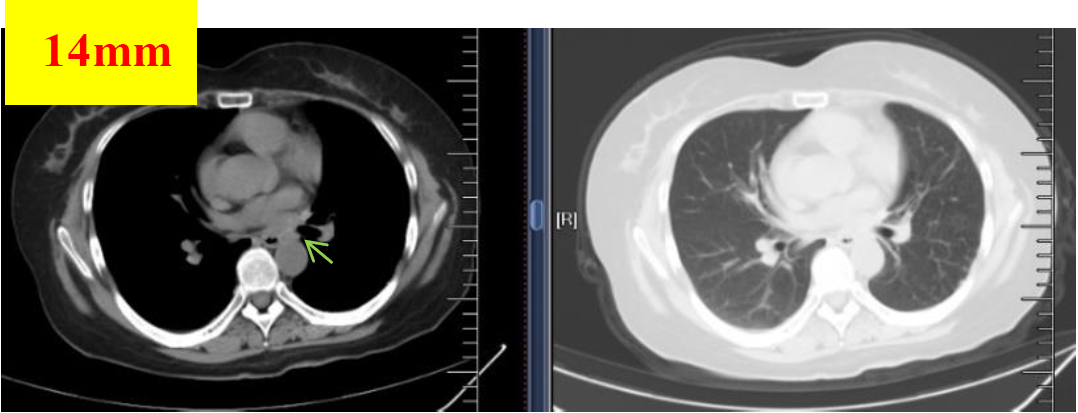

图6 2018.12.04影像学检查(PR)

图7 2019.01.06影像学检查(PR)